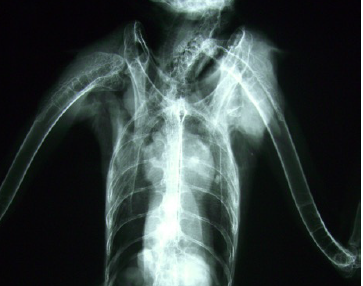

Is this a male or a female? Why?

Female

The long bones are bright = reproductive system = metabolically active tissue = female